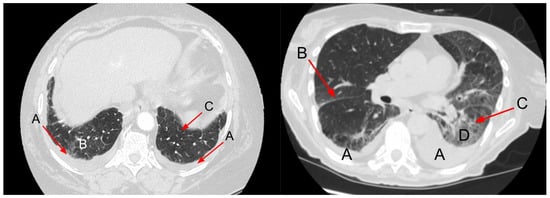

4. Chest CT

- Lewin, S.; Goldberg, L.; Dec, G.W. The Spectrum of Pulmonary Abnormalities on Computed Chest Tomographic Imaging in Patients with Advanced Heart Failure. Am. J. Cardiol. 2000, 86, 98–100. [Google Scholar] [CrossRef]

- Scillia, P.; Delcroix, M.; Lejeune, P.; Mélot, C.; Struyven, J.; Naeije, R.; Gevenois, P.A. Hydrostatic Pulmonary Edema: Evaluation with Thin-Section CT in Dogs. Radiology 1999, 211, 161–168. [Google Scholar] [CrossRef]

- Ribeiro, C.M.C.; Marchiori, E.; Rodrigues, R.; Gasparetto, E.; Souza, A.S., Jr.; Escuissato, D.; Nobre, L.F.; Zanetti, G.; de Araujo Neto, C.; Irion, K. Hydrostatic Pulmonary Edema: High-Resolution Computed Tomography Aspects. J. Bras. Pneumol. 2006, 32, 515–522. [Google Scholar] [CrossRef]

- Scillia, P.; Bankier, A.A.; Gevenois, P.A. Computed Tomography Assessment of Lung Structure and Function in Pulmonary Edema. Crit. Rev. Comput. Tomogr. 2004, 45, 293–307. [Google Scholar] [CrossRef]

- Dayem, H.A.; Gohari, A.; Endo, Y.; Shwarzberg, H.; Afari, A.; Waite, S.A. Chest Computed Tomography Features Predictive of Elevated B-Type Natriuretic Peptide Independent of Renal Function: Diagnostic Implications for Evaluation of Congestive Heart Failure. J. Comput. Assist. Tomogr. 2013, 37, 760–764. [Google Scholar] [CrossRef]